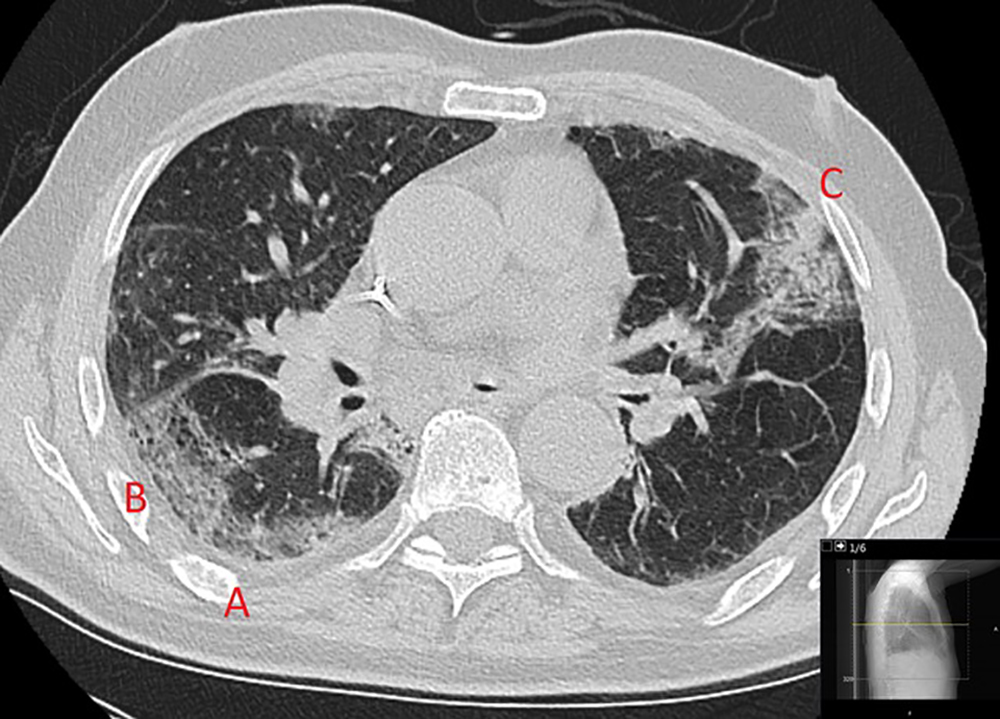

Lungorna är ett av de organ som drabbas hårt av det nya coronaviruset. Parallellt ser sjukvård och forskare att det råder en skillnad mellan vad röntgenbilderna visar och hur patienten faktiskt mår.

– Studier visar att AI kan skilja covid-19 från andra typer av lunginflammation. Vårt mål är att förbättra träffsäkerheten i diagnostiken ytterligare, säger Mats Danielsson, professor i medicinsk bildteknik vid KTH.

Tillsammans med professor Kevin Smith arbetar Mats Danielsson på det nystartade Medtechlabs som har världsledande kompetens inom medicinska bilder och AI. Och nu ska bildanalys och AI rädda fler coronapatienter.